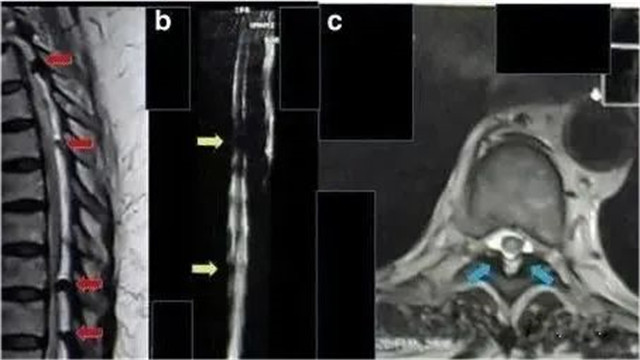

2017年(nián)海(hǎi)外(wài)報(bào)道(dào)一(yī)例6γε≥←2歲的(de)印尼籍婦女(nǚ),被診斷為(wèi)胸部截癱、'≥φ慢(màn)性腎功能(néng)衰竭、糖尿病,長(cháng)γ©期腎髒受累,慢(màn)性腎功能(néng)衰竭2年(n☆₽λián),肌酐水(shuǐ)平為(wèi)11mg/dL,無小(xiǎo)便。

采用(yòng)間(jiān)充質幹細胞移植方案治療。鞘內(nèi)注射1 ↓∑♣.6×10^7個(gè)間(jiān)充質幹細胞,靜(jìng)脈注射1.6×10^7個(g€δ¥>è)間(jiān)充質幹細胞。

△ 患者胸部磁共振成像顯示,脊髓受到(dào)多(duō)處壓↑÷迫

鞘內(nèi)注射和(hé)靜(jìng)脈注射後三周後,患者可(kě)以移動腳趾,®★₹β腎功能(néng)得(de)到(dào)改善。肌酐✔₩水(shuǐ)平降至9 mg/dL。8個(g₽←'×è)月(yuè)後,患者可(kě)以擡起腿,肌酐水≥®♥↑(shuǐ)平是(shì)2mg/dL,小(xiǎo)便恢複正常。